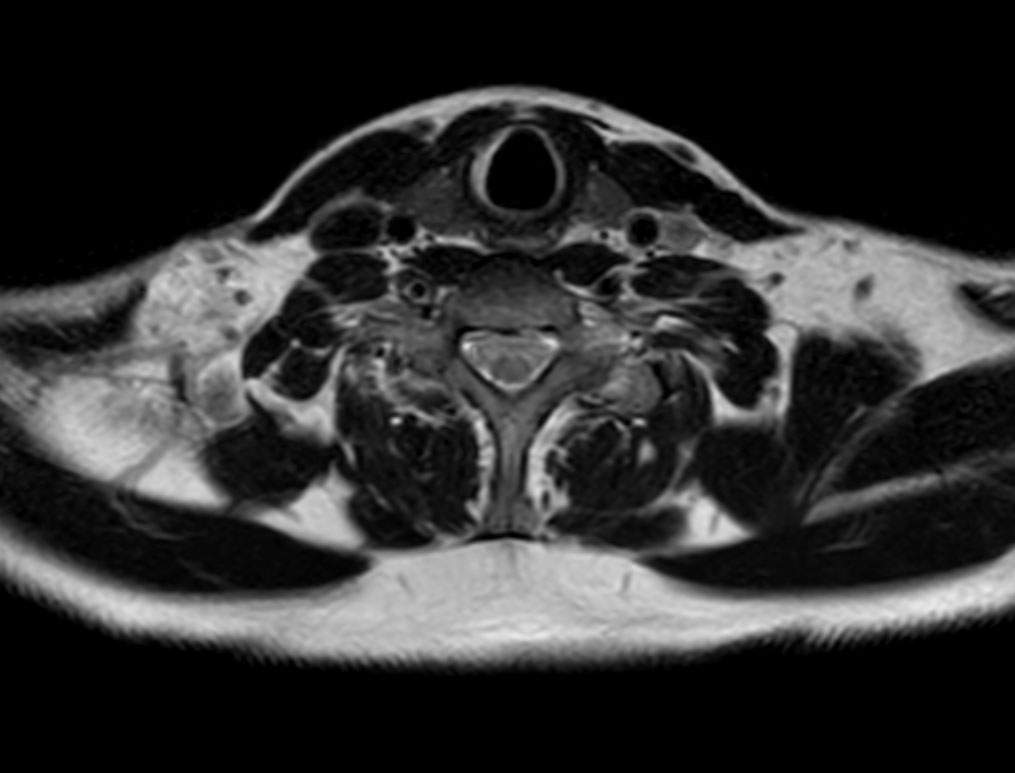

Axial T1w TSE